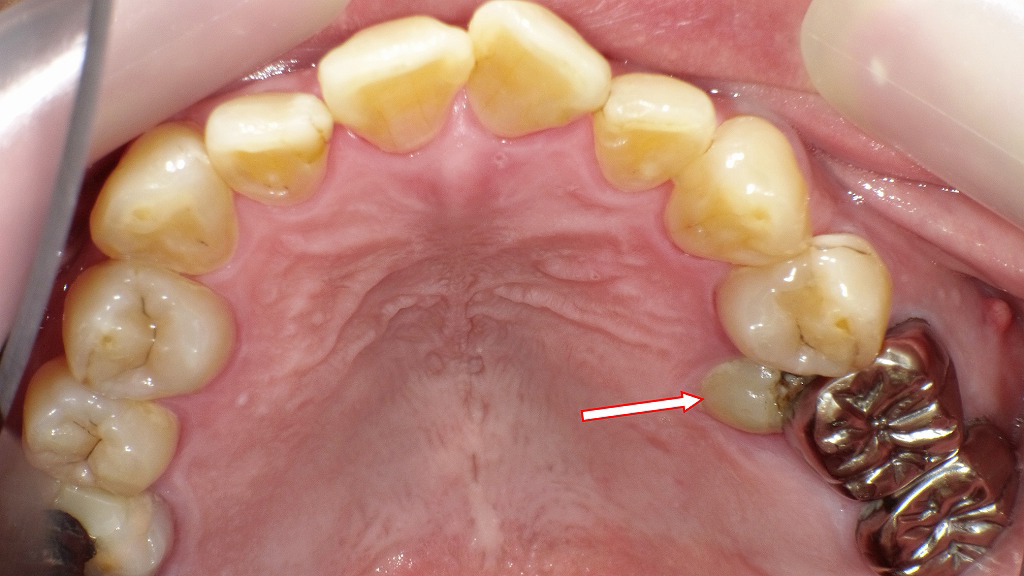

小臼歯が埋伏歯となった口腔内写真

この口腔内写真は、同症例の上顎(うわあご)歯列を撮影したものです。

赤い矢印で示された部位には、**上顎の第二小臼歯が埋伏歯(まいふくし)**として確認されます。以下に詳細を説明します👇

🦷 観察ポイント

- 矢印の先に見える部分は、**歯ぐきからわずかに露出した歯冠(しかん)**です。

- 歯の大部分はまだ歯ぐきと骨の中に埋まっている状態で、完全には萌出していません。

- 手前の第一小臼歯と銀歯(大臼歯のクラウン)との間にスペースがなく、「半埋伏歯」の状態です。

- 食片やプラークが溜まりやすく、歯ぐきの腫れや炎症、虫歯リスクが高まることもあります⚠️

🩺 対応・治療の考え方

- CTやパノラマレントゲンで歯の傾きや骨との位置関係を確認することが必要です。

- 萌出スペースがあれば矯正的に引き出すことも可能ですが、

隣接歯に影響する場合や炎症がある場合は抜歯の検討も行われます。 - いずれにしても、早期に歯科での精密診査を受けることが大切です。